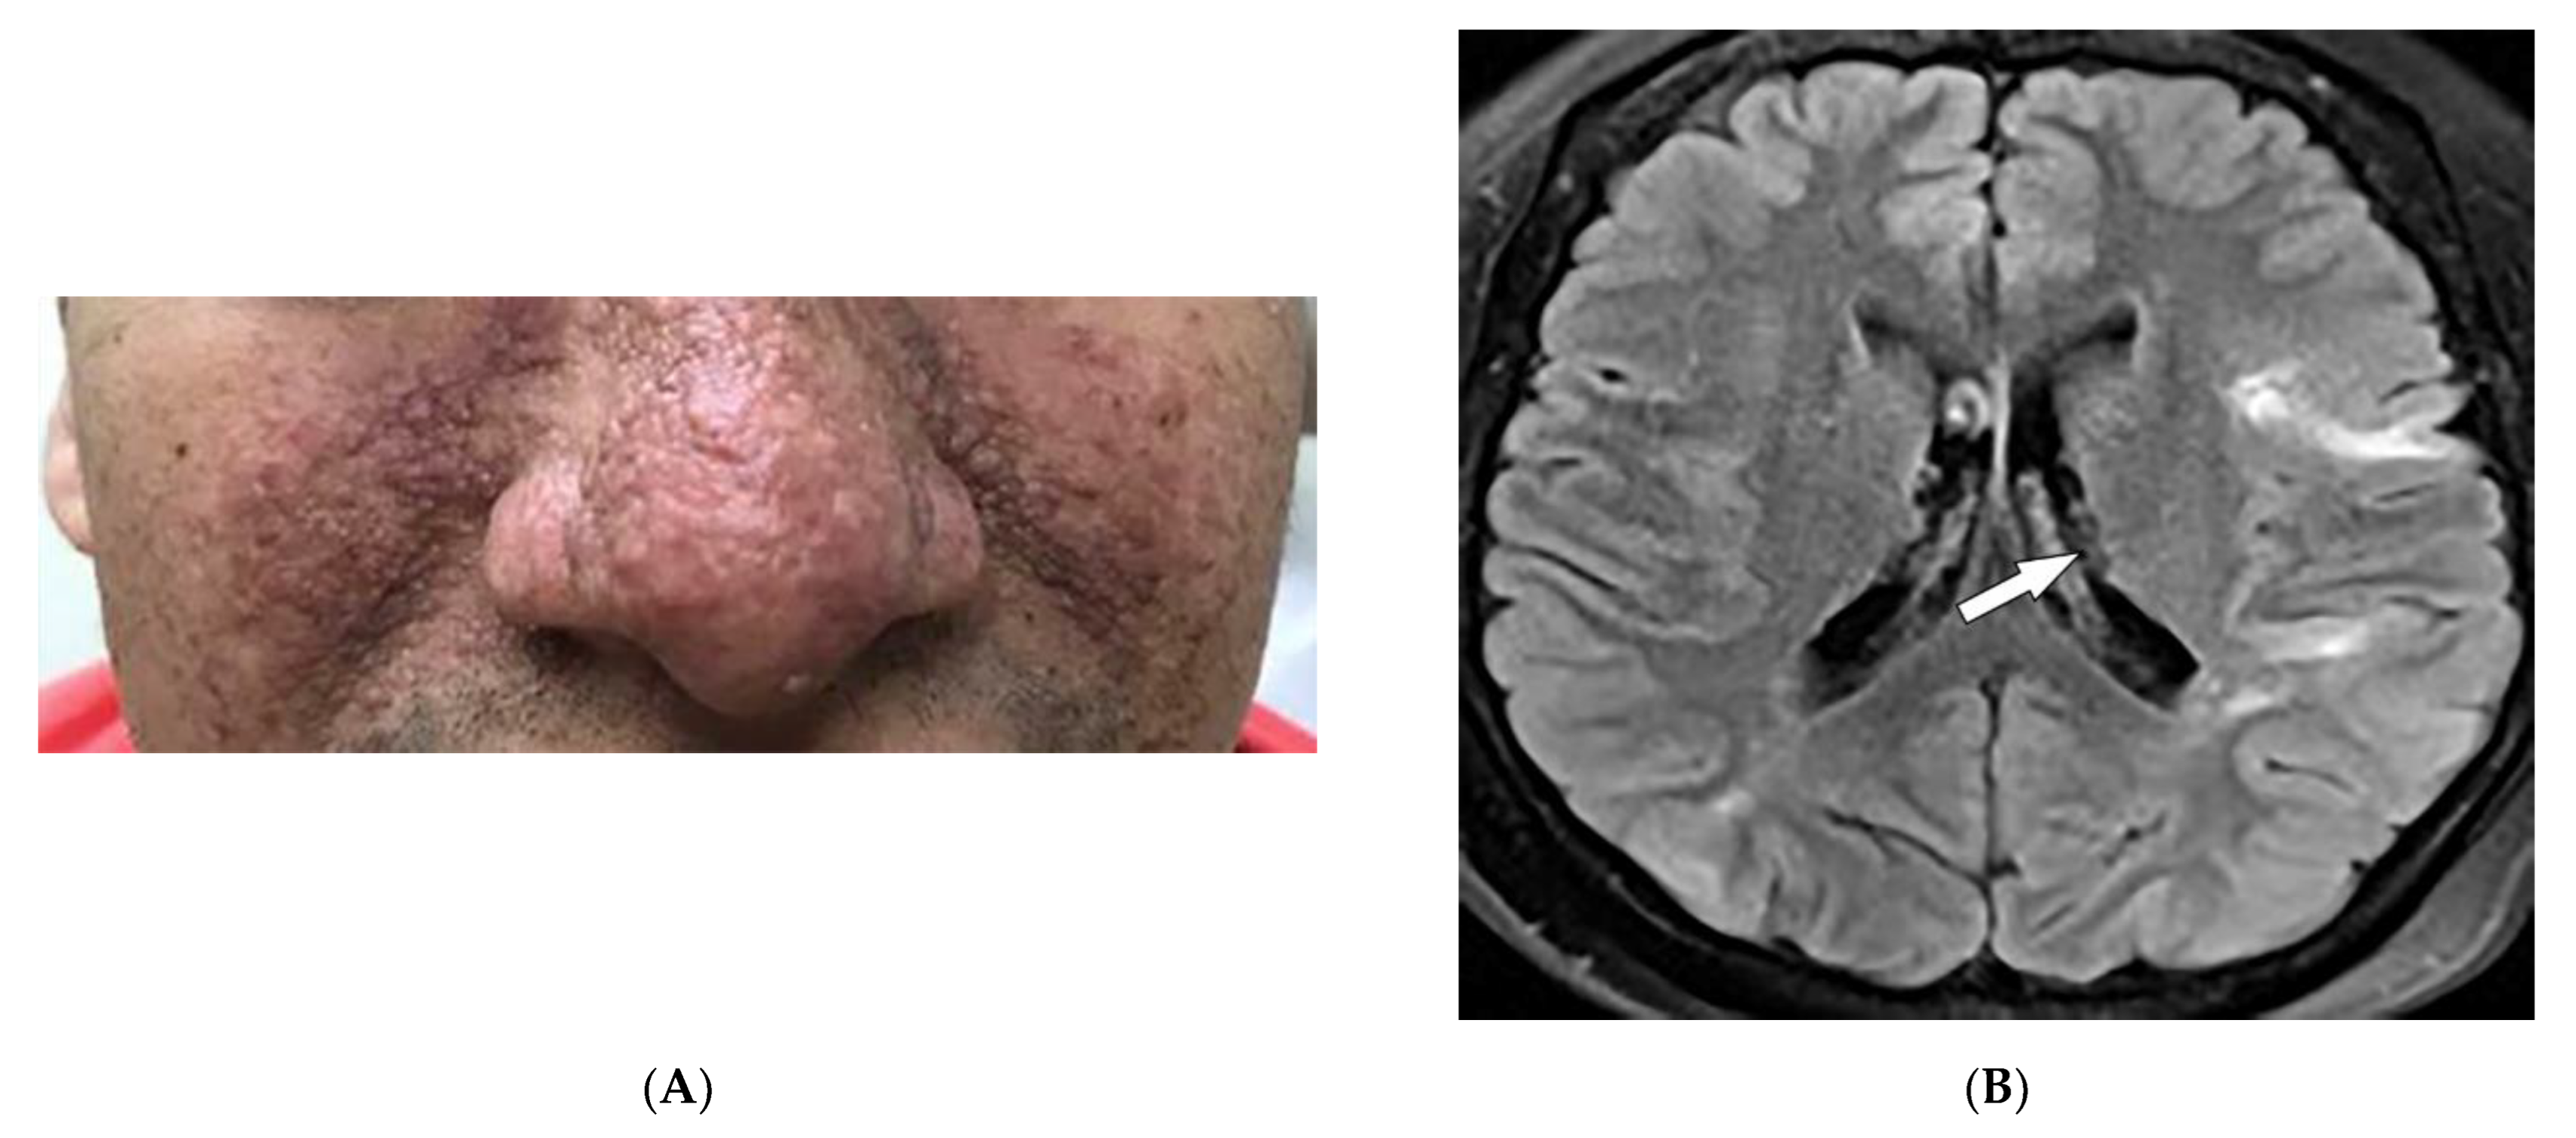

2.2. Sarcoidosis

| Sarcoidosis | Lupus pernio Erythema nodosum Lung nodules and adenopathy neurosarcoidosis Bone lesions | Reticulonodular lung opacities with upper lobe and peri-lymphatic distribution Leptomeningeal enhancement Lacy lytic bone lesions |

| Kaposi sarcoma | Erythematous or violaceous macules, plaques, nodules Pulmonary involvement Gastrointestinal involvement | Nodular enhancing masses Peribroncovascular nodules and halo sign |